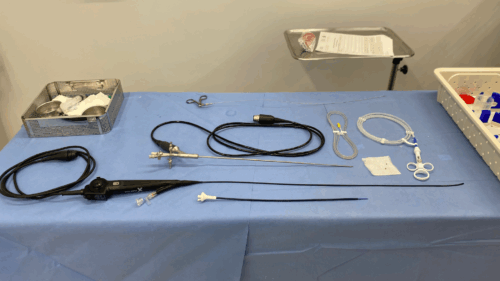

A ureteroscopia flexível com laser de alta potência é um procedimento endoscópico, ou seja, realizado por dentro do corpo, sem necessidade de cortes externos. O aparelho flexível navega por todo o sistema coletor do rim, acessando a pedra diretamente através da uretra.

O procedimento é realizado por via uretral, com introdução do aparelho até o rim. Uma bainha ureteral é usada para criar um canal de trabalho, por onde passam os instrumentos e o soro fisiológico usado na irrigação. Isso permite visualização constante durante a cirurgia.

Embora a ureteroscopia flexível com laser seja uma técnica bem difundida entre os urologistas, o uso do laser de alta potência requer familiaridade com o equipamento e seus ajustes.

Além do laser em si, novas tecnologias têm sido incorporadas ao procedimento, como as bainhas de aspiração, que permitem a remoção dos fragmentos enquanto o cálculo é fragmentado. Isso reduz o tempo cirúrgico, melhora a visualização do cirurgião e diminui a pressão dentro do rim, tornando a cirurgia ainda mais eficiente.